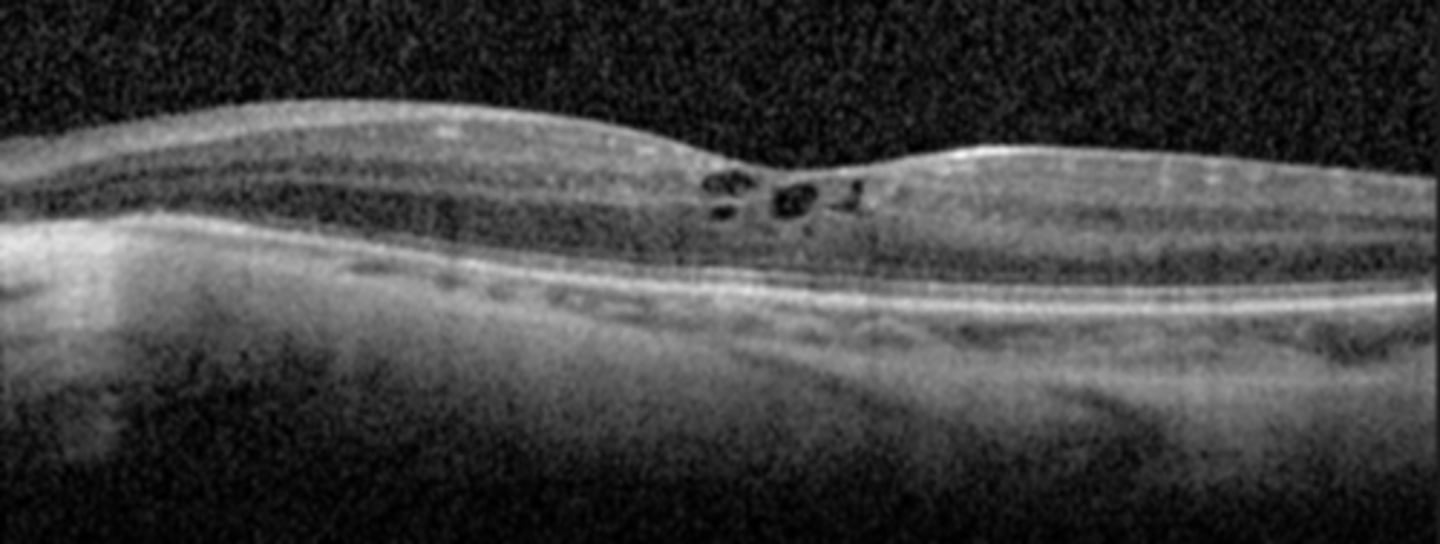

How does RP appear on OCT?

cystic macular lesions, ERM, VMT in some RP pt's with reduced central VA - may have outer>inner retinal layer thinning

What feature of RP sine pigmento is seen here?

perifoveal loss of PR's and RPE on OCT = ring scotoma very close to fixation seen on HVF

What feature of sectoral RP is seen here?

still has PIL loss and RPE thinning on OCT